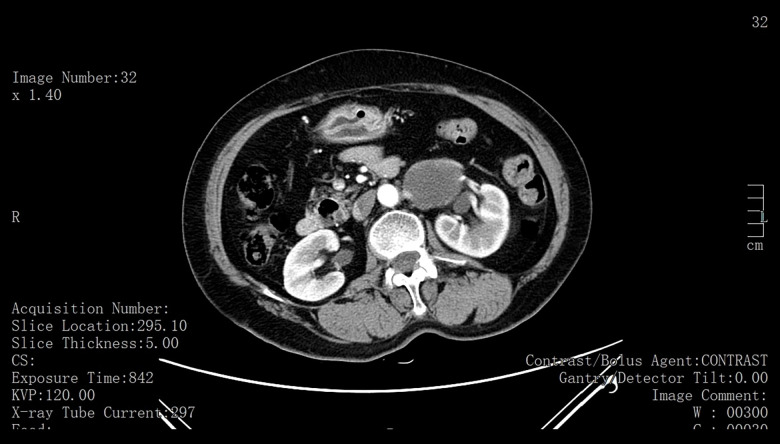

BACKGROUND Primary retroperitoneal tumors (PRTs) are uncommon, with retroperitoneal dermoid cysts being particularly rare. The cystic cavity of mature cystic teratomas (dermoid cysts) is lined with squamous epithelium and primarily filled with sebaceous material. These lesions often lack specific symptoms, leading to delayed diagnosis. Imaging modalities such as computed tomography (CT) and magnetic resonance imaging (MRI) are crucial for identifying these lesions, but definitive diagnosis relies on pathological examination. Surgical resection is the primary treatment, particularly for symptomatic or enlarging lesions. This report describes a case of a 78-year-old woman presenting with hydronephrosis secondary to a solitary retroperitoneal mature cystic teratoma (dermoid cyst) removed by laparoscopic resection. CASE REPORT A 78-year-old woman presented with left renal occupancy and severe hydronephrosis detected during routine health screening. Imaging studies revealed a retroperitoneal cystic mass compressing the upper urinary tract. She underwent laparoscopic resection of the mass and nephrectomy. Histopathological examination confirmed the diagnosis of an isolated retroperitoneal mature cystic teratoma. Postoperatively, she recovered well and remained asymptomatic during follow-up. CONCLUSIONS Retroperitoneal dermoid cysts are rare and pose diagnostic challenges due to their nonspecific clinical and imaging features. Early diagnosis and surgical intervention are critical to preventing complications and preserving organ function. This case report discusses the importance of preoperative evaluation and early treatment, highlighting the urgency of optimizing and standardizing the diagnosis and management of such diseases.

背景:原发性腹膜后肿瘤(prt)并不常见,尤其是腹膜后皮样囊肿。成熟囊性畸胎瘤(皮样囊肿)的囊腔衬有鳞状上皮,主要充满皮脂腺物质。这些病变通常缺乏特异性症状,导致诊断延迟。计算机断层扫描(CT)和磁共振成像(MRI)等成像方式对于识别这些病变至关重要,但最终诊断依赖于病理检查。手术切除是主要的治疗方法,特别是对于有症状的或扩大的病变。本报告报告一位78岁的女性,以腹腔镜切除单发腹膜后成熟囊性畸胎瘤(皮样囊肿)继发肾积水。病例报告一名78岁女性,在常规健康检查中发现左肾占位和严重肾积水。影像学检查显示腹膜后囊性肿块压迫上尿路。她接受了腹腔镜肿块切除术和肾切除术。组织病理学检查证实了一个孤立的腹膜后成熟囊性畸胎瘤的诊断。术后恢复良好,随访期间无症状。结论腹膜后皮样囊肿是罕见的,由于其非特异性的临床和影像学特征,给诊断带来了挑战。早期诊断和手术干预对预防并发症和保持器官功能至关重要。本病例报告讨论了术前评估和早期治疗的重要性,强调了优化和规范此类疾病的诊断和管理的紧迫性。